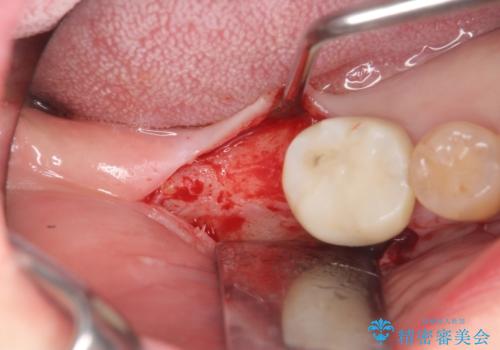

奥歯 インプラントによる機能回復

- 歯を欠損し、噛めないことの治療を希望され来院されました。

インプラントを用いて、しっかりとかめるような治療を計画します。

最後方臼歯はインプラントを用いることでしっかりと咬合機能を回復することができます。